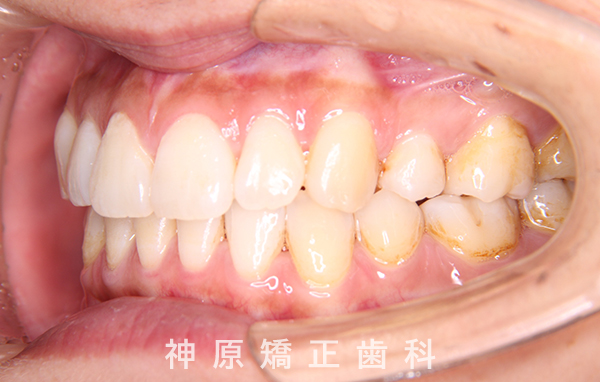

初診時

マルチブラケット装着1年後

治療終了

治療前と治療後